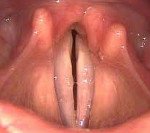

Снижение подвижности голосовых связок при нейропатическом парезе гортани приводит к нарушениям голосообразования (фонации) и дыхательной функции. Для нейропатического пареза гортани характерно последовательное вовлечение в патологический процесс внутренних гортанных мышц: вначале нарушается функция задней перстне-черпаловидной мышцы, отвечающей за расширение голосовой щели и отведение голосовых складок, затем развивается слабость и паралич аддукторов гортани, которые в норме суживают гортань и сводят голосовые связки. Данный феномен получил название закона Розенбаха - Семона. В соответствии с ним при нейропатическом парезе гортани за счет сохранившейся вначале заболевания работоспособности аддукторов голосовая связка на стороне поражения занимает срединное положение, спустя какое-то время нарастает слабость аддукторов и голосовая связка переходит в промежуточное положение.

Односторонний нейропатический парез гортани в начале характеризуется сохранностью фонации за счет примыкания здоровой голосовой связки к занимающей серединное положение связке пораженной стороны. Дыхание также остается нормальным, его затруднение может быть выявлено лишь при значительной физической нагрузке. Дальнейшее развитие нейропатического пареза гортани сопровождается вовлечением аддукторов гортани и промежуточным положением голосовой связки, за счет чего не происходит полного смыкания голосовой щели при фонации. Возникает охриплость голоса. Через несколько месяцев у пациентов с нейропатическим парезом гортани компенсаторно развивается гипераддукция голосовой связки на здоровой стороне и она начинает плотнее прилегать к паретичной связке. В результате отмечается восстановление обычного звучания голоса, однако нарушения вокальной функции у пациентов с нейропатическим парезом гортани сохраняются.

Двусторонний нейропатический парез гортани в начальном периоде сопровождается выраженными дыхательными нарушениями вплоть до асфиксии. Это связано с тем, что обе голосовые связки занимают срединное положение и могут полностью смыкаться, препятствуя прохождению воздуха в дыхательные пути. Клинически двусторонний нейропатический парез гортани проявляется редким шумным дыханием с втяжением надключичных ямок, надчревья и межреберных промежутков на вдохе и выпячиванием их на выдохе. Пациент с двусторонним нейропатическим парезом гортани находится в вынужденном положении, чаще сидя, опираясь руками на край дивана. Выражение его лица отражает крайний испуг, кожные покровы имеют цианотичную окраску. Даже незначительное физическое усилие вызывает резкое ухудшение состояния. Через 2-3 дня от начала клинических проявлений нейропатического пареза гортани голосовые связки принимают промежуточное положение и между ними образуется щель. Дыхательная функция улучшается, но любая физическая нагрузка приводит к появлению симптомов гипоксии.